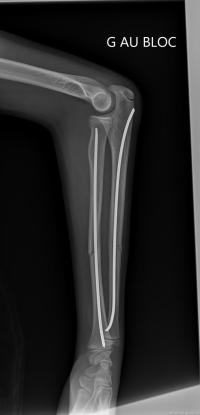

Fracture de l’avant-bras 31 mars 202519 mars 2024 par Damien Traitement Traitement orthopédique Embrochage centro-médullaire